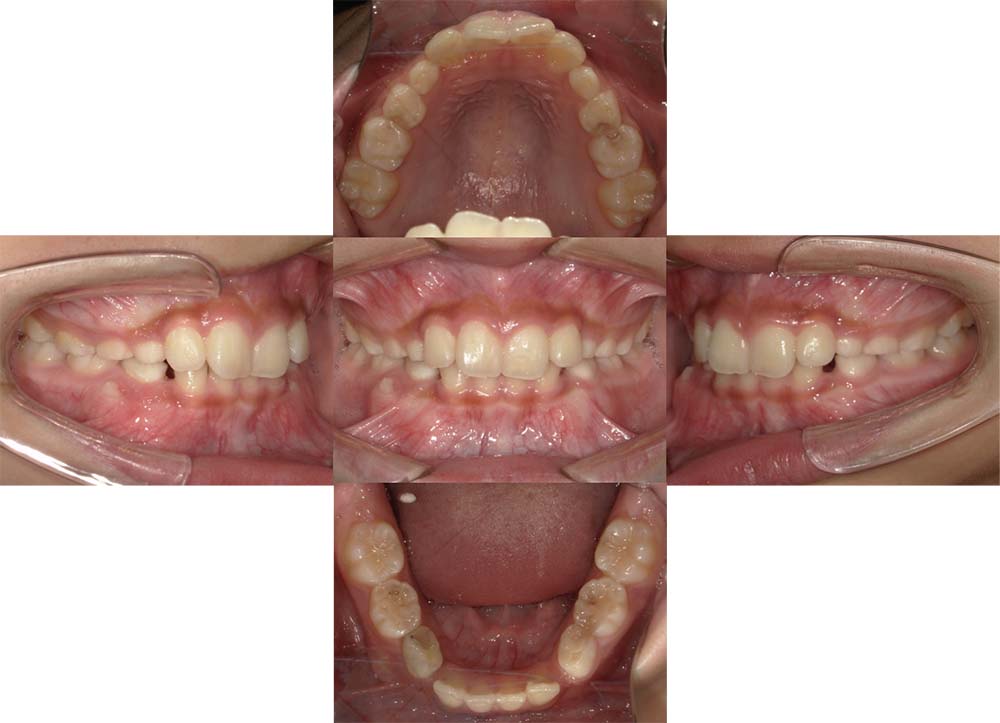

症例01

| 主訴 | 歯並びがガタガタしている。 |

| 診断名あるいは主な症状 | 叢生 |

| 年齢/性別 | 22歳・男性 |

| 矯正ステージ | 大人の矯正治療 |

| 治療方法 | ワイヤー矯正 |

| 抜歯部位/抜歯有無 | 非抜歯 |

| 治療内容 | 上顎大臼歯の遠心移動により前歯のガタガタを排列スペースを獲得し全顎的な排列を行った。 |

| 費用 | 85万円程度(2025.10時点の料金となります。) ※矯正基本料金、審美ブラケットを含む |

| 治療期間 | 2年4ヶ月 |

| 主なリスク・副作用 | 痛み、歯根吸収、歯肉退縮、虫歯、後戻り |